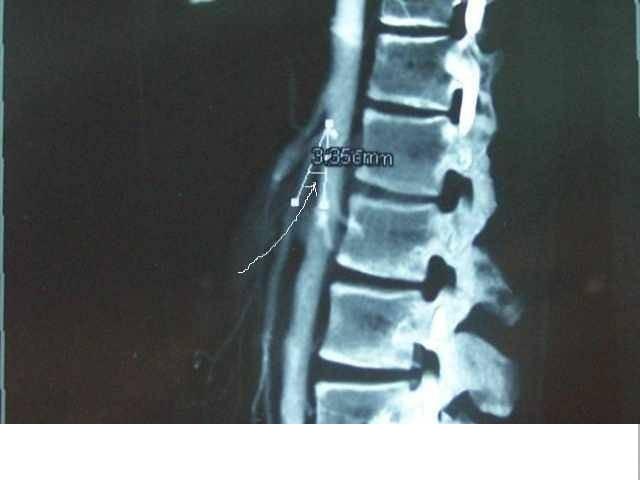

此综合征又名Wilkie 综合征、肠系膜上动脉综合征、主动脉肠系膜动脉压迫综合征和慢性十二指肠淤滞症。这是少见的一种十二指肠水平部和/或上升部位梗阻。1927 年Wilkie 收集报告75 例慢性十二指肠梗阻,指出其是具有特征的综合征,表现为进食后上腹痛、嗳气、饱胀,常伴有大量的呕吐物。症状为间隙性发作,持续1~2d,此后可以缓解数周。慢性病程常使病人体重明显下降和消瘦,有半数病人在发作时如果病人取左卧位或俯卧胸膝位可使症状得到部分缓解。故文献中称Wilkie综合征。 一、病因 肠系膜上动脉从腹主动脉腹侧发出走向尾侧方向,它与腹主动脉形成45°向尾侧开口角,十二指肠水平部和上升部正好位于此夹角之间。此处十二指肠背侧为腹主动脉,其腹侧为肠系膜上动脉,水平部十二指肠的头侧为胰腺钩突部和左肾静脉,并有脂肪组织。由于有一定量脂肪组织,在直立位和卧位时使肠系膜上动脉与腹主动脉间夹角得以相持,使十二指肠水平部不受肠系膜上动脉和腹主动脉的 压迫,保持肠管畅通,如果夹角为6~25°,则发生Wilkie综合征。此外,Treitz韧带起于胸10椎体横膈,终于十二指肠上升部与空肠交界处。Treitz韧带为平滑肌纤维和结缔组织构成,其长度不一,如Treitz韧带较短,则十二指肠上升部上提,水平部就位于肠系膜上动脉与腹主动脉夹角较深处,则也易发生动脉压迫和梗阻,尤其在仰平卧位或直立位时。故十二指肠夹在主动脉和肠系膜上动脉之间距离正常为10~20mm,在Wilkie综合征时减少为2~8mm。 发生Wilkie综合征既有属正常的解剖学素质性原因,又有病理性诱发因素存在,诱发因素集中在主动脉肠系膜上动脉夹角变小或两者之距离缩短方面,如体重过度下降疾病:肠道吸收不良、大面积烧伤后期、多发生创伤、脊柱骨折过度伸展复位固定、胰腺炎和腹主动脉瘤。最使人困惑的是精神病引起厌食呕吐,也可以引起高度消瘦和体重下降,发生十二指肠压迫,如无明确的精神病学诊断和治疗,即使手术治疗也不能得到治疗效果。 二、诊断 病史中体重下降和消瘦存在甚为突出,且80%病例为瘦长体型。临床上Wilkie综合征多为慢性,但有亚急性或急性发作。在发作期吞钡检查可见十二指肠降部和水平部扩张有梗阻,非发作期吞钡检查可能没有定论,但是用低张十二指肠造影术多有确定结果。俯卧胸膝位同时对下腹部向头侧和背侧加压(Hayes手法)皆有助于梗阻缓解,使钡剂通过。胃镜检查不能作出此诊断,但常发现胃窦炎、消化性溃疡(占25%~45%)。CT可以观察到腹主动脉和肠系膜上动脉夹角间脂肪组织缩小,其距离可测得,且伴有降部和水平部十二指肠扩张。超声检查或动脉造影侧位片在第三腰椎椎体水平可显示主动脉与肠系膜上动脉的夹角测定。除诊断十二指肠存在器质性淤滞外,尚需排除精神病引起的厌食呕吐和体重明显下降存在。有明确的诱因发生Wilkie综合征时,如腹主动脉瘤、脊柱骨折过度伸展复位固定、大面积烧伤恢复期严重消瘦等,应该加以确定,因为治疗主要针对此等诱因。 三、治疗 有些Wilkie 综合征病例可能在发作缓解期已经剖腹探查术,仅发现十二指肠稍肥厚扩张外,可能得“阴性”结论。Wilkie综合征在急性或亚急性发作梗阻时,原则上是首先用非手术保守治疗,胃管减压和液体电解质失衡纠正,尤其是有明确诱因时,非手术保守治疗目的是使体重上升和营养不良得以纠正。营养支持开始时应该用TPN,然后在梗阻缓解后用肠内营养,经鼻留置专用肠内营养导管,当导管进入十二指肠后取胸膝俯卧位,使螺旋状导管顶端通过十二指肠水平部进入空肠。然后用输液泵24小时连续输注营养液。Wilkie综合征如为精神病引起的厌食呕吐和消瘦,需要较长时间观察后会诊,同时给予合适药物治疗和非手术保守治疗。 如果Wilkie综合征为慢性有多年病程,非手术治疗不能达到体重上升和梗阻缓解,最终才考虑手术治疗。手术适应证为:①保守治疗失败;②长期慢性病史不能进食,消瘦,且十二指肠扩张明显;③合并有消化性溃疡。手术方式为空肠十二指肠吻合术。在小儿病例仅离断Treitz韧带,并游离十二指肠水平部和上升部,有报告得到较好效果,但十二指肠空肠吻合术简单可行,效果可靠。近十年来已有腹腔镜下施行十二指肠空肠吻合术报告,显然创伤小和恢复较快为其优点。